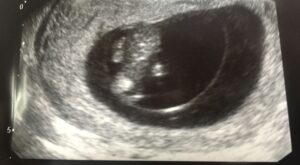

Sera positiva ayudaaa

Non classé

hay 9 años